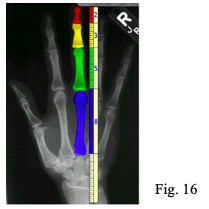

Basti pensare alla struttura anatomica del piede dove le due parti diseguali o segmenti sono rappresentate da (fig. 19):

Se misurando i due segmenti a e b (Rx, strumenti chirurgici…) e applicando la formula:

Si ottiene il rapporto 1,618 allora possiamo dire che il piede in esame è proporzionale, funzionale ed esteticamente bello. Per quanto concerne più da vicino, cioè nell’apparato di moto, è stato rilevato che il numero d’oro è il valore del rapporto fra il piano della sezione massima della coscia e la superficie plantare del piede rispetto al ginocchio.